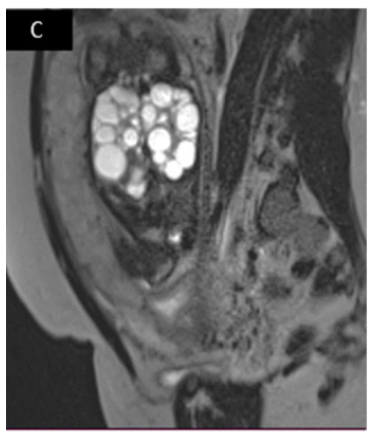

Antenatal Diagnosis of Bilateral Multicystic Kidney Dysplasia: Two Case Reports

Fatima Chait, Najlae Lrhorfi, Nourrelhouda Bahlouli, Rachida Chehrastane, Nazik Allali, Siham El Haddad and Latifa Chat. 12(5): 50-55.